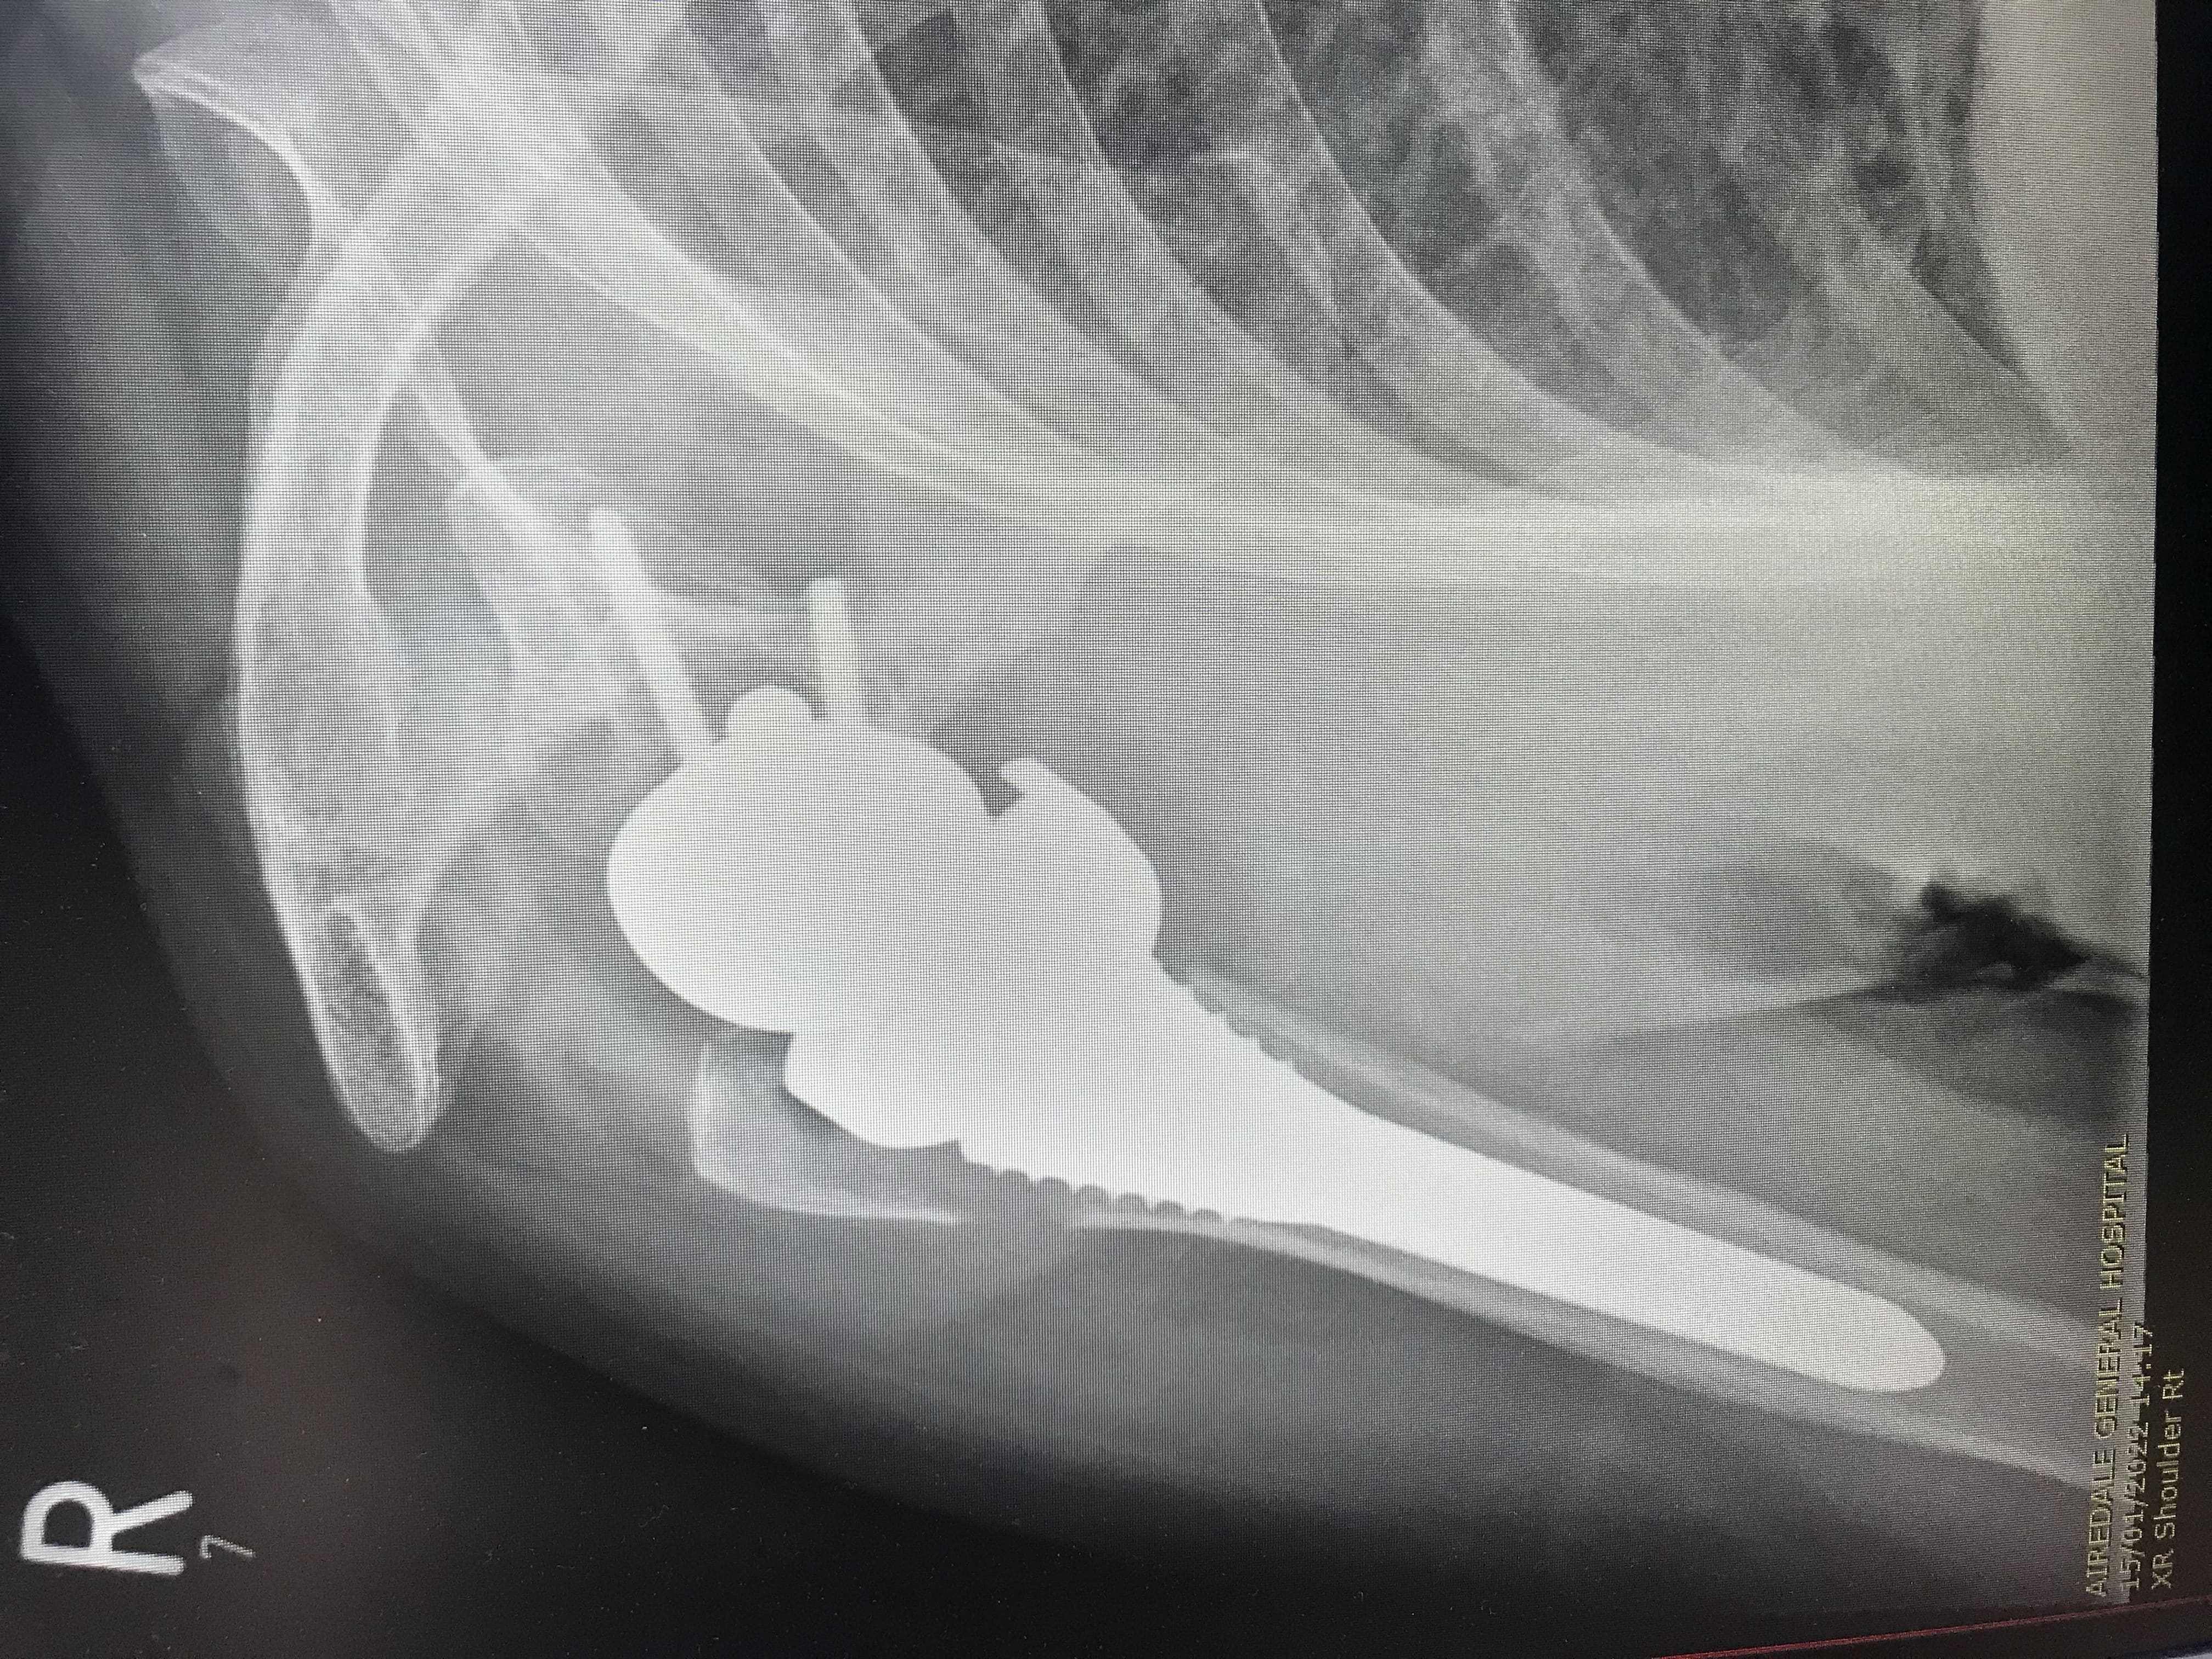

Images of Shoulder Replacement:

X-Ray of Knee Replacement 1